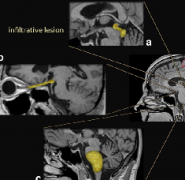

小儿丘脑肿瘤的更佳外科治疗方法是哪种?

小儿丘脑肿瘤常被认为是无法手术的。但是,现代显微外科技术以及神经影像学的改进使得能够进行准确的术前计划,可以以更顺利的方式进行切除...